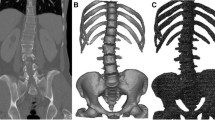

Estimation errors of Ferguson angles were 1.34° ± 1.51° for Model-1 and 2.07° ± 2.20° for Model-2, showing 35 % smaller error when using the proposed line of action. For a more complete analysis of the accuracy of the models to estimate the spine shapes, estimation errors of LOC (E LOC) of the individual vertebrae were obtained (Fig. 8). E LOC was calculated as Euclidian distance between LOCs given by the models and those measured on the X-rays. E LOC of 504 vertebraeFootnote 6 were 0.51 ± 0.41 mm for Model-1 and 1.41 ± 1.09 mm for Model-2, showing 64 % smaller error by our line of action. According to the above results, we hypothesized that the mean value of errors of Ferguson angles by Model-1 was smaller than that by Model-2, and we also made the same hypothesis for E LOC. The null hypotheses (H0) stood for the difference in the other direction. Paired Student’s t test was adopted to test the hypotheses. For the confidence level of 0.05, strong evidence was found against the null hypotheses, showing that our line of action can result in more accurate estimates of Ferguson angles of each spine region and E LOC of each vertebra, p-values of 0.0005 and 0.0000, respectively. Overall, it can be concluded that the personalization using our line of action can result in better estimates of the spine shape in the bending positions.

Consideration of the spine curvature as a chain of micro-scale motion segments allowed us to perform a deep analysis of the spine movement. The analysis provided profound insight into the movement to formulate our concept of the line of action. It was shown that the spine model (Model-1) personalized by using the proposed line of action could make better estimates of the spine shape in the lateral bending positions than Model-2; reduction in E LOC by 0.90 mm. This reduction is important as it can have noticeable effects on how well the simulated spines fit a patient’s spine in a position. For example, Fig. 9 illustrates the simulated spines with about 0.90 mm difference in E LOC for the left bending position of one of our patients. As can be seen, this example shows that such an enhancement could be influential in fitting (i.e. the similarity between the spine curvatures) and estimating Ferguson angle (error of 0.85° vs. 4.28°). Therefore, our achievements in estimation of the locations of the vertebrae (0.90 mm less errors) can be noticeable. It should also be noted that the standard deviations of the estimation errors were also reduced by about three times, showing effective reduction in error of LOC (please see the box charts in Fig. 8). Therefore, our line of action can result in better estimates of the spine shape in the lateral bending positions.